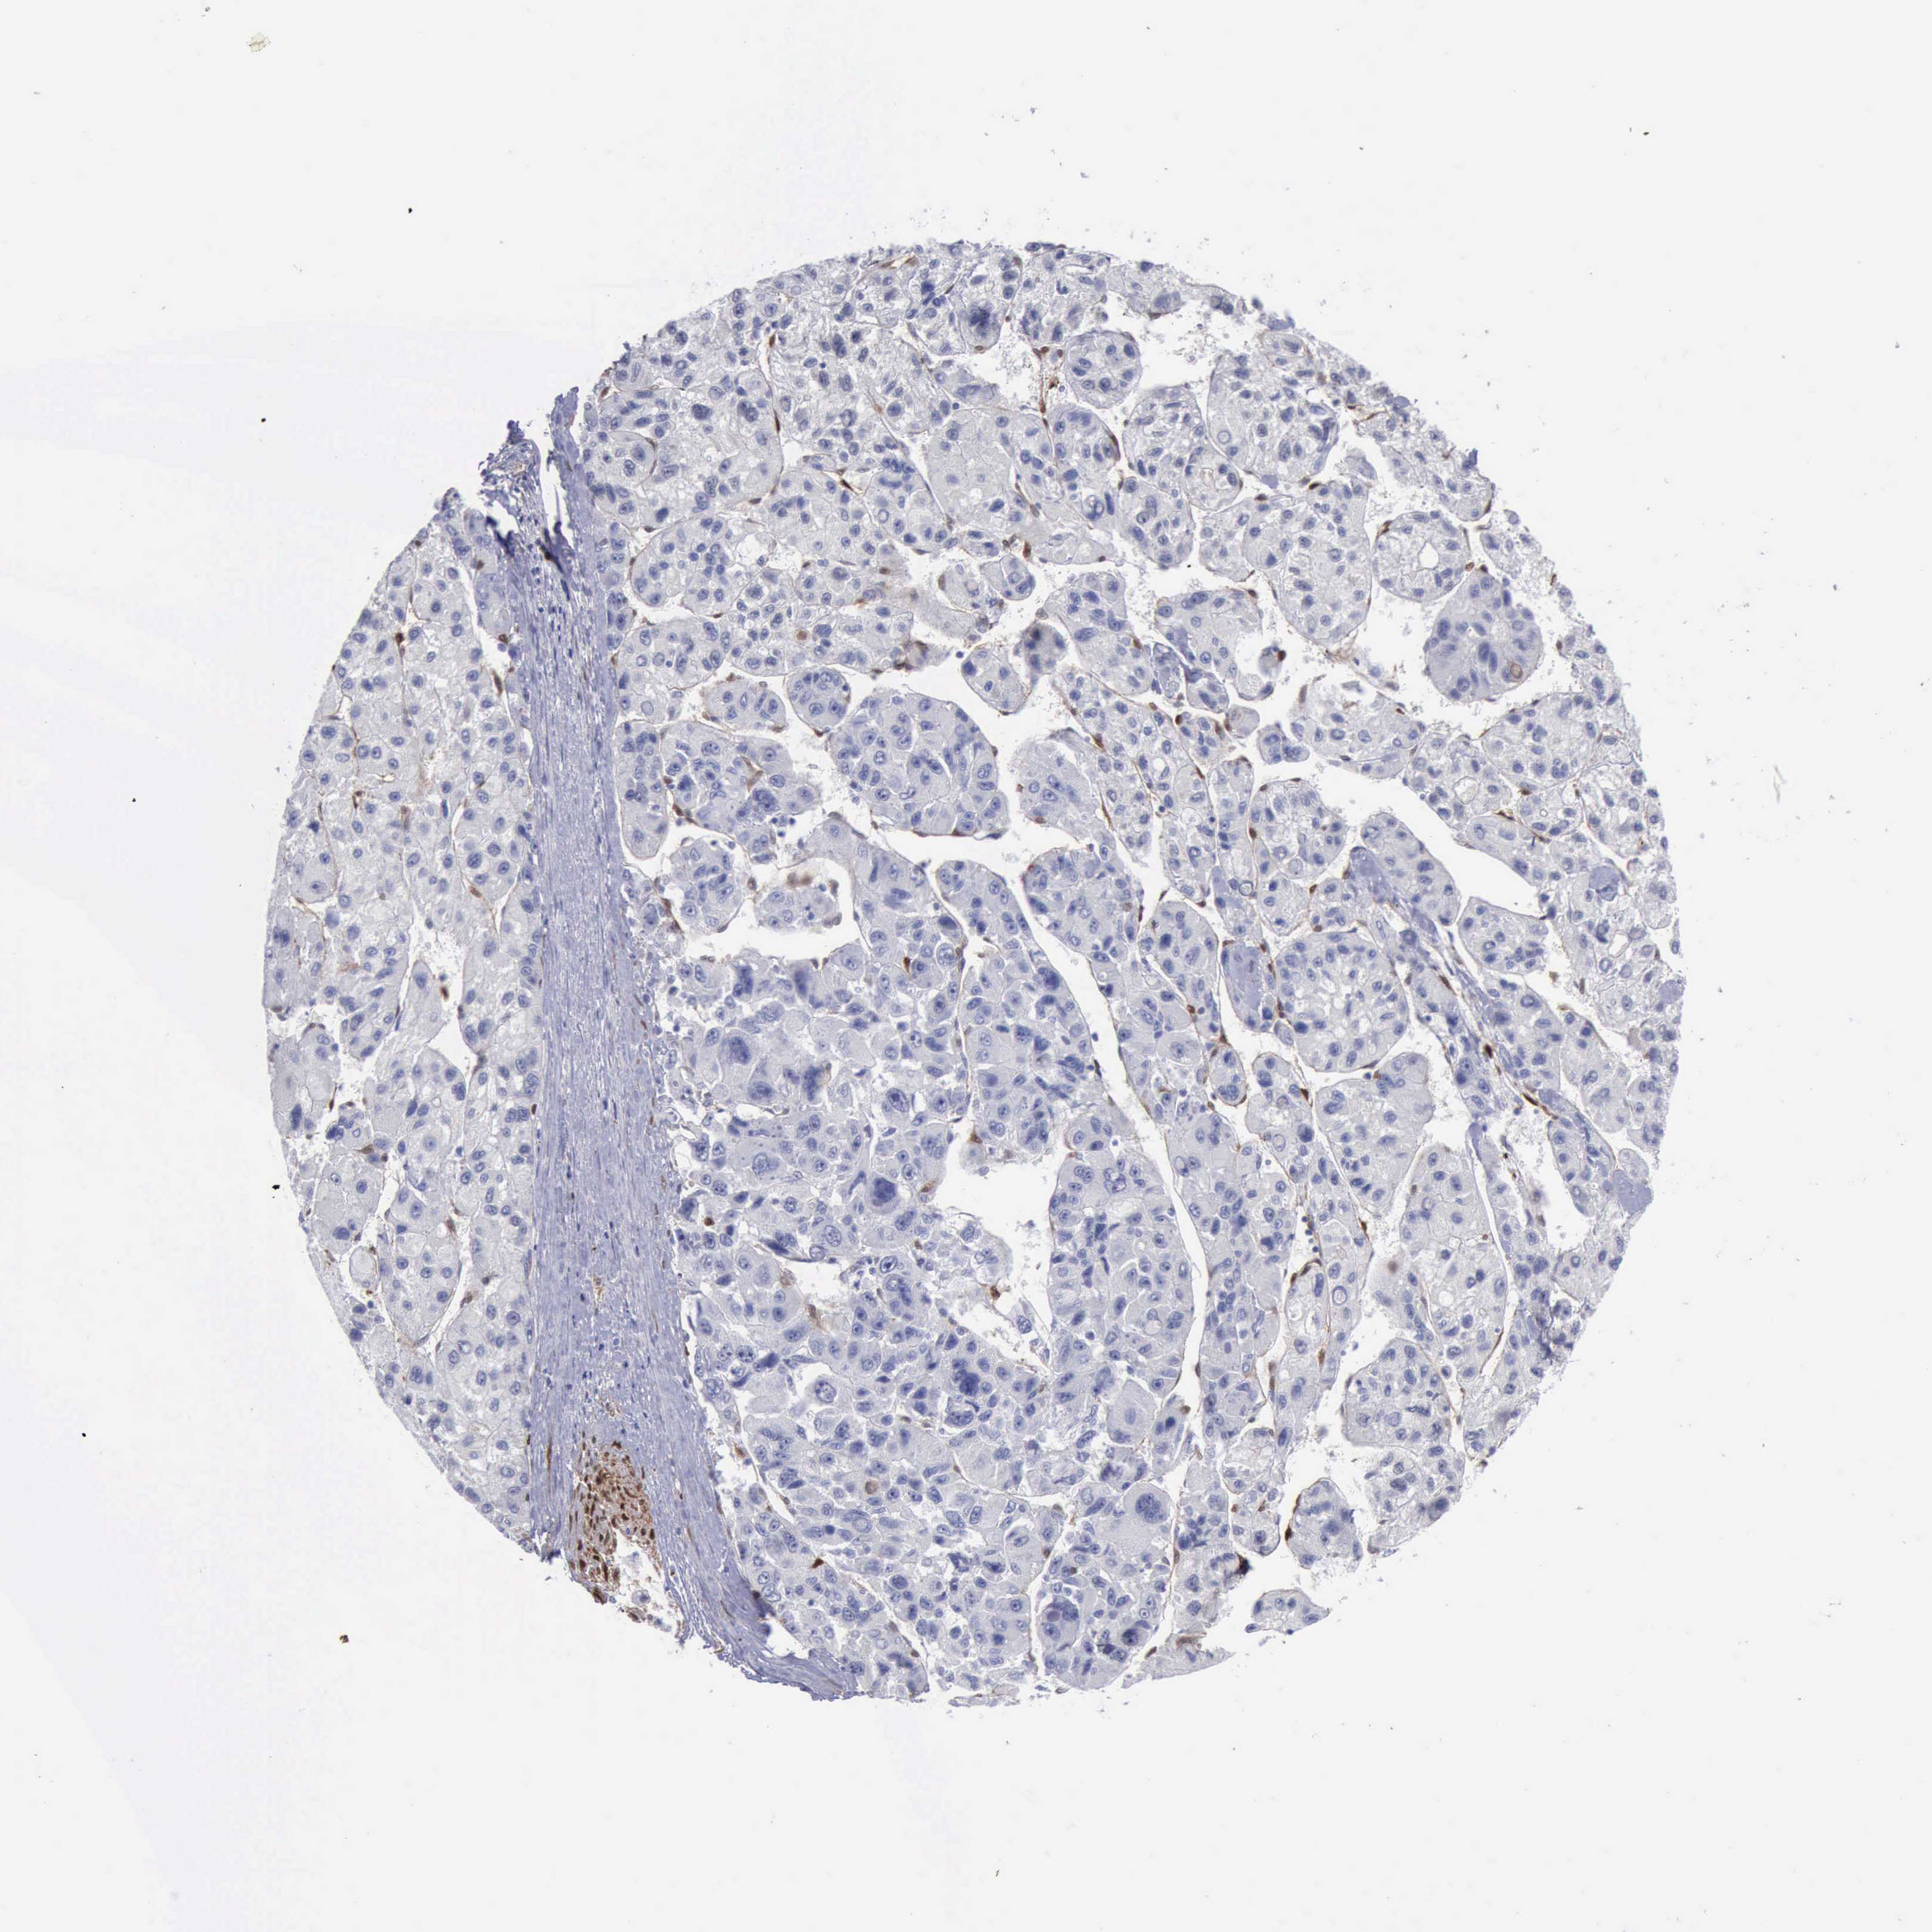

LIVER CANCER - Protein expressioni

A mouse-over function shows sample information and annotation data. Click on an image to view it in a full screen mode. Samples can be filtered based on level of antibody staining by selecting one or several of the following categories: high, medium, low and not detected. The assay and annotation is described here.

Note that samples used for immunohistochemistry by the Human Protein Atlas do not correspond to samples in the TCGA dataset.

Antibody stainingi

Antibody staining in the annotated cell types in the current human tissue is reported as not detected, low, medium, or high, based on conventional immunohistochemistry profiling in selected tissues. This score is based on the combination of the staining intensity and fraction of stained cells.

Each image is clickable and will lead to virtual microscopy that enables deeper exploration of all samples and also displays staining intensity scores, fraction scores and subcellular localization as well as patient and tissue information for each sample.

Antibody HPA001040

Antibody HPA001391

Antibody CAB020817

Staining

High

Medium

Low

Not detected

Intensity

Strong

Moderate

Weak

Negative

Quantity

>75%

75%-25%

<25%

None

Location

Nuclear

Cytoplasmic/membranous

Cytoplasmic/membranous,nuclear

Carcinoma, Hepatocellular, NOS

Cholangiocarcinoma